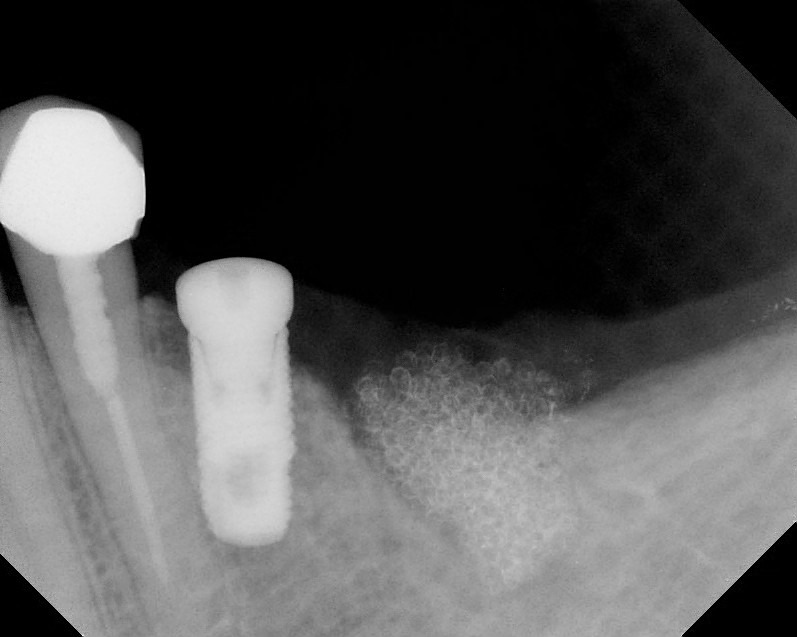

Implants

This treatment involves implanting artificial dental roots, and restoring dental crown without damaging the adjacent teeth.